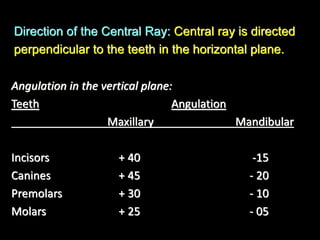

1. The document discusses various intra-oral radiographic techniques including the paralleling cone technique and bisecting angle technique.

2. The paralleling cone technique provides accurate images with little magnification and no superimposition but is more difficult for patients. The bisecting angle technique is easier for patients but results in more image distortion.